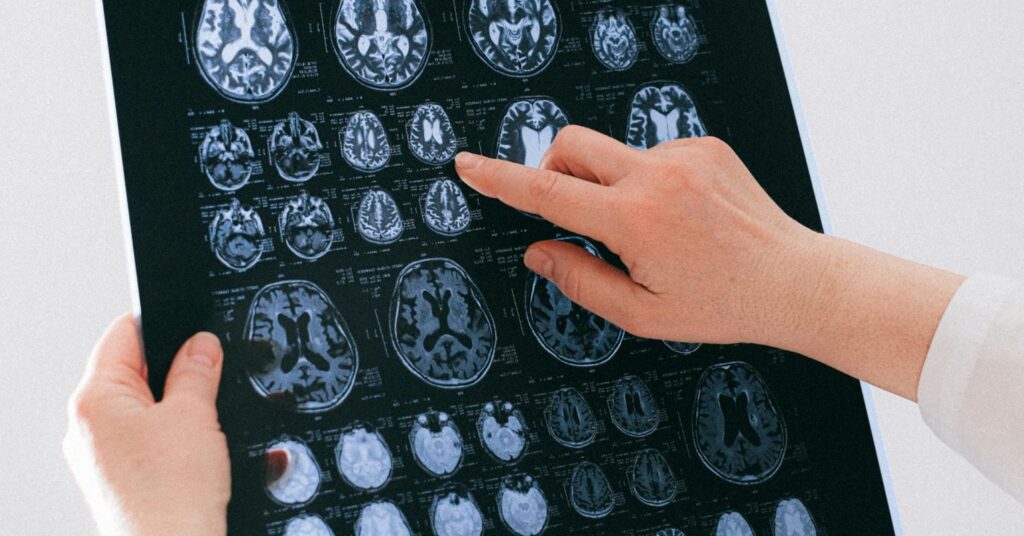

As part of a large, multi-site study, rather than relying on symptom questionnaires (though they were gathered separately but not used in analyses), structural brain scans (MRIs) from two sets of children with ADHD, 446 in a discovery group and 554 in a follow-up validation group, were compared with controls comprised of children without ADHD.

Complex analyses used metrics that identified targeted features across the brain structures that represent how they function within larger brain networks, namely degree centrality, nodal efficiency, and participation coefficient, which roughly translates into the number of connections, efficiency in signaling, and how well they communicate with other functional brain regions, respectively. These metrics were used to develop morphometric similarity networks (MSNs), identifying individualized networks across structures to examine variations and their similarities, and how they interact. Such analyses can identify distinct “hubs,” particularly influential coupling patterns.

When it came to identifying ADHD-specific patterns, as the study’s authors described it, their analyses allowed them to compare the brain metric results for ADHD participants with the non-ADHD control group’s metric, which they liken to pediatric growth charts used to locate where a child’s height lands in terms of the degree to which it varies from population expectations for other children that age. This individualized, brain data-driven approach provides a different view of ADHD than symptom checklists. The results from the discovery sample children were confirmed in the follow-up validation study.